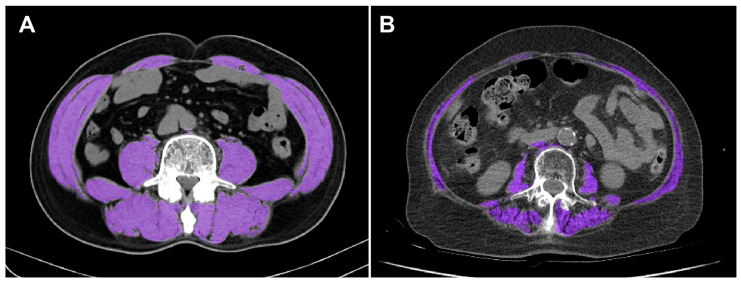

Background/Objectives: Sarcopenia, the age-related decline in skeletal muscle mass and function, is increasingly recognized as an important prognostic factor among elderly patients. This study aimed to evaluate whether computed tomography (CT)-defined sarcopenia independently predicts short-term mortality in elderly Korean trauma patients. Methods: We retrospectively analyzed 722 patients aged ≥65 years admitted to a Korean Level I trauma center between January 2020 and December 2021. Sarcopenia was defined as the lowest sex-specific quartile of skeletal muscle index (SMI) measured at the third lumbar vertebra (L3) within 7 days of admission. Demographics, injury severity, and outcome variables were compared between groups. Kaplan-Meier survival analysis with a 24 h landmark and multivariable Cox regression were applied to identify independent predictors of 30-day mortality. Results: Among 722 patients, 181 (25.1%) were sarcopenic. They were older and had lower body mass index and serum albumin yet showed lower Injury Severity Score (ISS) at presentation. Despite this, in-hospital mortality was higher in sarcopenic patients (15.5% vs. 9.8%, p = 0.036), while 24 h mortality did not differ (4.4% vs. 3.7%, p = 0.663). Landmark analysis starting at 24 h demonstrated significantly worse 30-day survival in the sarcopenia group (log-rank p = 0.028). Multivariable Cox regression confirmed sarcopenia as an independent predictor of 30-day mortality (HR, 2.36; 95% CI, 1.07-5.23; p = 0.034), along with higher ISS and lower Glasgow Coma Scale (GCS) scores. Conclusions: CT-defined sarcopenia at the L3 level independently predicts 30-day mortality in elderly trauma patients and may support early risk stratification.